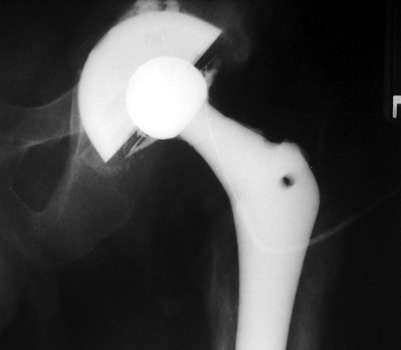

Normal arthrogram

Aspiration of hip after removal of prosthesis. Needle placed

at femoral edge where fluid collects. Needle should not be placed in acetabular

area, which may not be fully intact, risking needle entry into pelvic cavity.